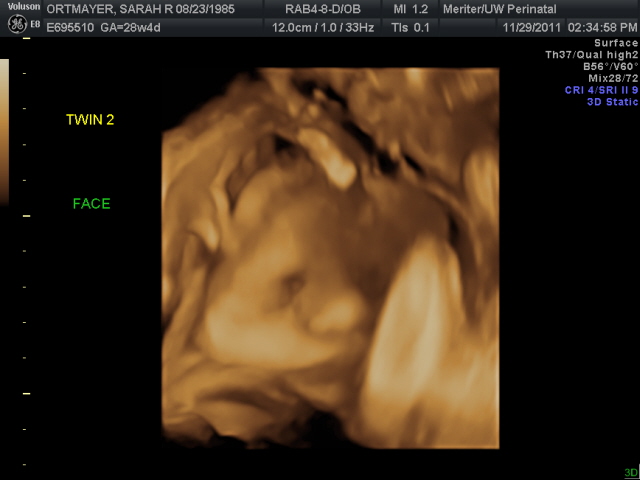

Yesterday was my 28 week growth scan, my sister got to come a long and see her first ultrasound! It was awesome! The babies were so active and acting more and more like newborns. Within the first minute we got to see baby "A" give a HUGE yawn and then proceed to either kiss or bite his brother :) Both boys were head down, although baby "B" did two big flips during the ultrasound he ended the show head down again. Here are a few pictures from the ultrasound:

Baby "A" profile